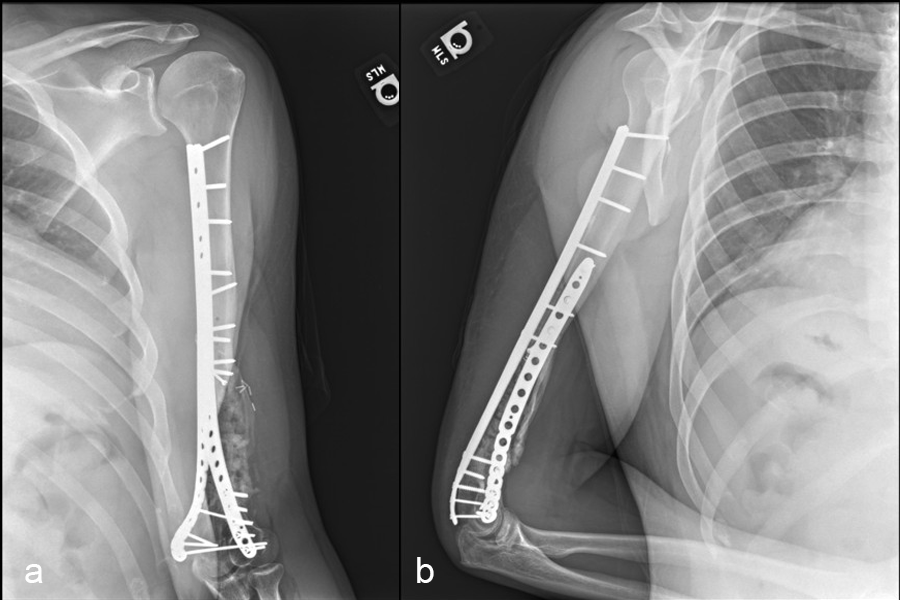

Healing progressed well over the following 9 months (Fig 23 - 27). The patient’s pain was well controlled in the early postoperative phase, and he was weaned off the prescribed narcotics after four weeks. He remained smoke free for the first four weeks and then admitted to re-starting his vaping. His elbow ROM improved significantly to 20-125 and good supination/pronation.